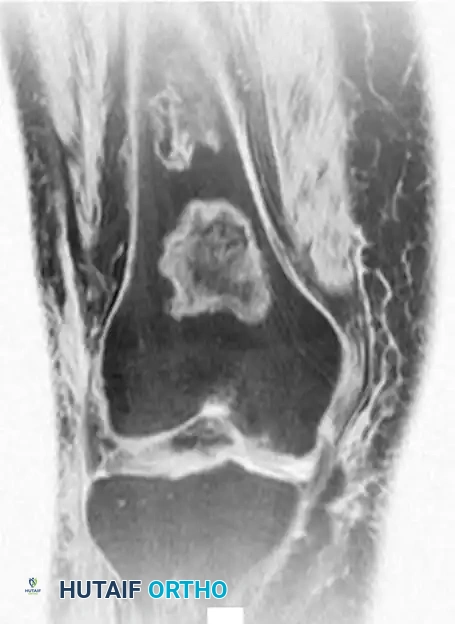

Fig. 20-22: (A and B) Pathological fracture of the right proximal tibia occurring through a large, expansile “brown tumor” of hyperparathyroidism in a 55-year-old woman.

Primary treatment is medical or surgical management of the underlying endocrinopathy (e.g., parathyroidectomy) by an endocrinologist or general surgeon. Following normalization of PTH levels, brown tumors typically remineralize and regress spontaneously. Orthopedic intervention is strictly limited to the stabilization of actual or impending pathological fractures. If a fracture occurs, intramedullary nailing or rigid plate osteosynthesis is required, as the structural integrity of the bone is severely compromised.